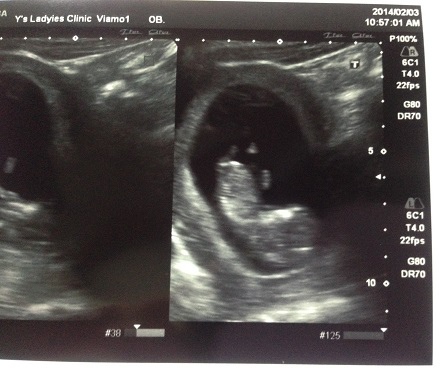

第二次產檢:大頭一個?

2月3日 (11W5D)

到了診所一樣先量血壓+驗尿後 等醫生看診

這次要來看上回抽血的報告.....很擔心不知道自己有沒有風疹抗體(德國麻疹)